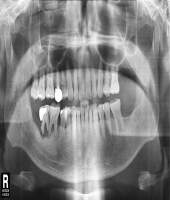

| ● 진료과목 : [심미보철] 돌출치아의 치료

| ● 내용 : 사고로 인한 돌출치아의 치료 |